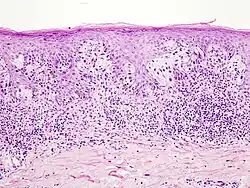

Akrolentiginöses Melanom

Angesichts seines Entstehungsorts an der Handinnenfläche oder der Fußsohle scheint Sonnenlicht für diesen Melanomtyp ursächlich nicht oder nur von geringer Bedeutung zu sein.

In der horizontalen Wachstumsphase besteht eine auf die Epidermis begrenzte Vermehrung von Melanozyten, die zumeist groß sind und ebenfalls deutlich vergrößerte, gelegentlich bizarre Zellkerne aufweisen. Das Zytoplasma enthält Melaningranula in wechselnder Menge und Form. Besonders in der basalen Epidermis gelegene Tumorzellen weisen häufig auffällige Dendriten auf. Die atypischen Melanozyten breiten sich in einzelzelliger Lagerung entlang der Junktionszone und in die Tiefe entlang der Ausführungsgänge der Schweißdrüsen aus.

In länger bestehenden Tumoren finden sich vermehrt auch große melanozytäre Nester entlang der Junktionszone und einzelne oder in Nestern gelagerte Melanozyten in den oberen Zelllagen der Epidermis, eventuell mit Ausschleusung durch die überliegend verbreiterte Hornschicht. Die Epidermis zeigte eine Akanthose (Verbreiterung) und verlängerte Retezapfen.

In der vertikalen Wachstumsphase finden sich häufig spindelzellige Melanozyten in der Dermis. Letztere zeigt eine desmoplastische Reaktion.[46]

- Akrolentiginöses Melanom

-

Verlängerte Retezapfen der Epidermis -

Große Tumorzellen mit vielgestaltigen Zellkernen